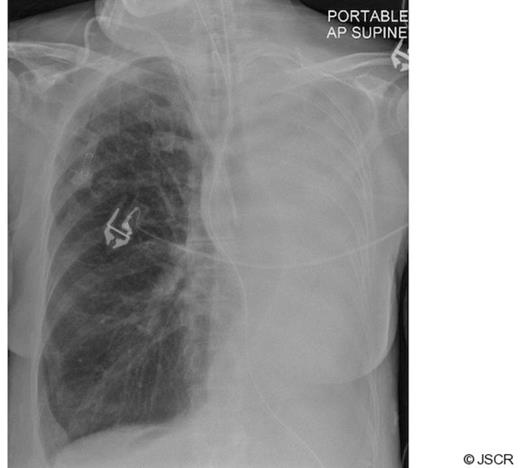

A 77 year old lady presented after an episode of chest pain and dyspnoea. Clinical examination was unremarkable apart from a low grade temperature of 37.8 oC and breath sounds were equal bilaterally. There was no evidence of cardiac ischaemia on an electrocardiogram. Inflammatory markers (white cell count and C-reactive protein) were raised. The cardiac enzyme levels were within normal limits. Empirical antibiotic therapy was instituted for a clinical diagnosis of lower respiratory tract infection. After admission the patient's condition deteriorated with increasing dyspnoea and a worsening PaO2 / FiO2 ratio. Her chest radiograph showed a complete “white-out” of her left lung field (Fig 1). Her trachea was intubated and her lungs mechanically ventilated.